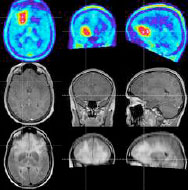

Gliome sind bösartige Hirntumoren, die aus den Stützzellen des zentralen Nervensystems entstehen, den so genannten Astrozyten. Bei der Behandlung bösartiger Hirntumoren entwickeln einige Patienten rasch Resistenzen gegen die Strahlen- und die medikamentöse Chemotherapie. Beide Behandlungen schädigen das Erbgut der Tumorzellen.

Die DNA-Defekte lösen wiederum das Selbstmordprogramm, die Apoptose, aus. Doch die Tumorzellen schützen sich mit einem effizienten Reparatursystem vor den Folgen der Therapie und damit vor dem Zelltod. Wissenschaftler aus dem DKFZ und dem Universitätsklinikum Heidelberg entdeckten eine Ursache für diese Therapieresistenz. Ließe sich dieser Resistenzmechanismus blockieren, könnten bösartige Hirntumoren möglicherweise wirkungsvoller behandelt werden.

(Quelle: Deutsches Krebsforschungszentrum, Bildquelle: Hirntumorhilfe; MRT eines Hirntumors)